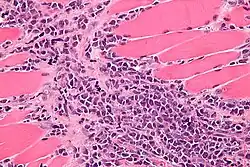

Le diagnostic associe l'imagerie médicale (scanner, TEP) et l'étude de la biopsie en l'anatomopathologie.